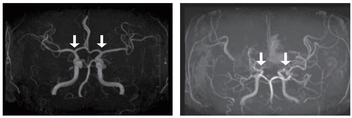

인제대학교 부산백병원(원장 양재욱)이 최신형 컴퓨터단층촬영장치(CT)와 자기공명영상장치(MRI)를 도입해 심뇌혈관 및 응급질환 진단 역량을 한층 강화했다. 특히 CT는 응급의료센터에 설치돼 뇌졸중과 심근경색 등 ‘골든타임’이 중요한 심뇌혈관 환자의 신속한 진단에 활용한다. 이는 최근 보건복지부가 지정한 ‘지역 심뇌혈관질환센터’ 운영에 더해 지역 내 심뇌혈관 응급의료 체계를 더욱 강화할 전망이다. 부산백병원은 3월부터 두 장비 모두 본격 운영에 들어갔다. CT장비 ‘Revolution APEX Elite’는 초고속 회전 기술과 넓은 검출 범위를 갖춘 최첨단 장비로, 기존 CT보다 빠르고 정밀한 영상 촬영이 가능하다. 0.23초의 초고속 회전 속도와 160mm의 넓은 촬영 범위를 갖춰 매우 짧은 시간 안에 심장과 뇌혈관을 정밀하게 촬영할 수 있는 것이 특징이다. 응급 뇌졸중 환자의 뇌혈류 상태를 확인하는 뇌관류(Perfusion) 검사를 빠르게 시행할 수 있으며, 심전도 장치(ECG) 부착 없이도 심장 촬영이 가능한 기술이 적용돼 심근경색과 같은 중증·응급 검사에서 신속한 검사가 가능하다. 함께 도입된 MRI장비 ‘SIGNA Premier 3.0T’는 딥러닝 기